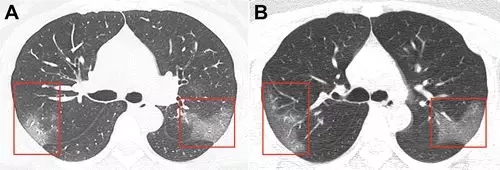

病例1,33岁女性,在武汉工作,

今年1月份回到兰州后

第二天开始发热,咳嗽,

5天后,她去医院检查,

她咽喉部分泌物中发现新冠病毒核酸,

肺部CT扫描(见下图A)

两侧肺上叶肺段呈斑片状毛玻璃样显影。

医生给她用了很多药物,

甚至用上了干扰素,

3天后,再次CT检查发现,

两肺的毛玻璃显影更大了(图片B),

显示治疗效果不好,病情加重。

01-2.webp

图片来自《Radiology》杂志